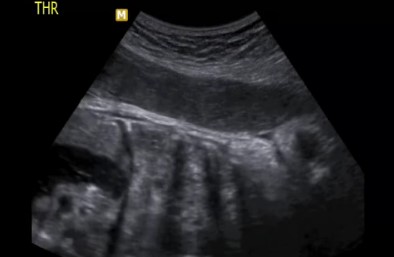

Este caso forma parte de nuestra Biblioteca de Casos lo importante es que esta anomalia le paso completamente desapercibida al medico referidor hasta las 33-34 semanas de embarazo cuando noto que algo en la silueta cardiaca no estaba bien. A continuacion el video. Esta bebe esta bien fue intervenida al nacimiento y no tenia alteraciones cromosomicas. El cariotipo habia salido normal.